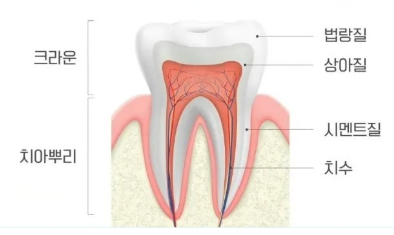

치간삭제란 치아의 가장 바깥층인 법랑질 일부를

미세하게 삭제하여 공간을 확보하는 방법입니다.

법랑질은 단단한 부위로 치아 구조 중에 가장 많은 부분을 차지합니다!!